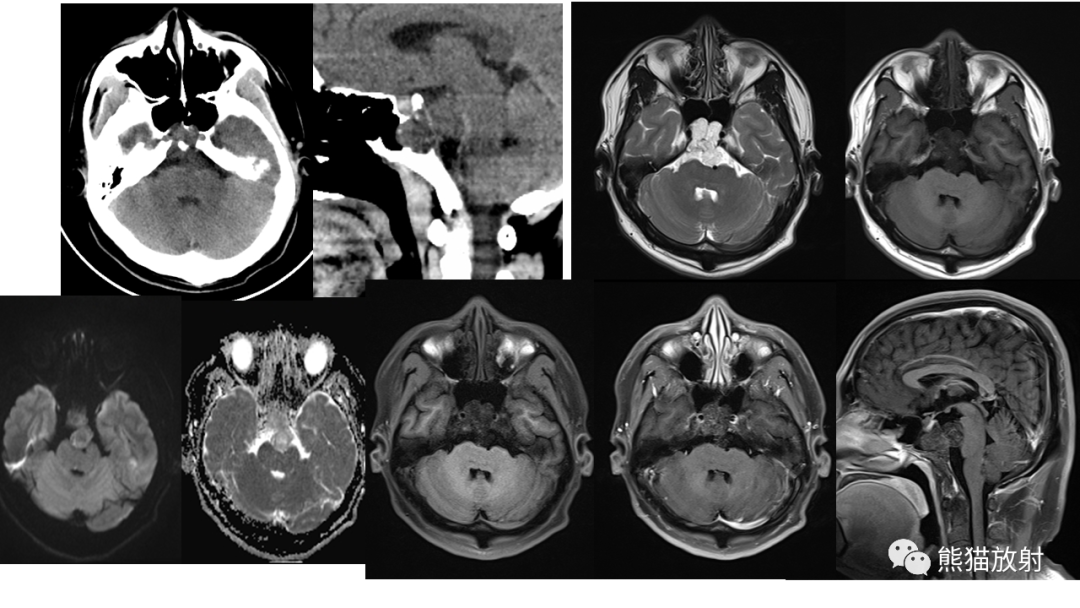

【病例】斜坡 & 骶骨脊索瘤各1例CT及MR-1

【病例】斜坡 & 骶骨脊索瘤各1例CT及MR-2